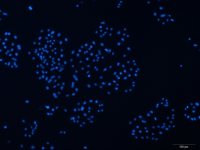

上皮样;多角形

贴壁生长

A-375人恶性黑色素瘤细胞描述:(1)所有细胞株购自ATCC;

(2) 公司可提供新鲜或冻存细胞株;

(3) 细胞株数量约 5×105/瓶;

(4) 不含有HIV-1、HBV、HCV、支原体、细菌、酵母和真菌。

A-375人恶性黑色素瘤细胞 保存和应用:客户可以根据自己的需求选择新鲜或者冻存的原代细胞,如是新鲜细胞株,客户收到细胞后应立即将其放入CO2细胞培养箱内静置后2-3h,再进行后续的实验操作。如是冻存细胞,客户收到细胞后应立即将其放入液氮、-80℃冰箱或立即进行复苏。A-375人恶性黑色素瘤细胞只用于科研,不得用于临床应用。